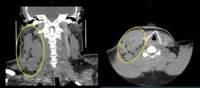

Classical Hodgkin lymphoma - CT scan

A CT scan of the neck shows extensive cervical adenopathy (circles).